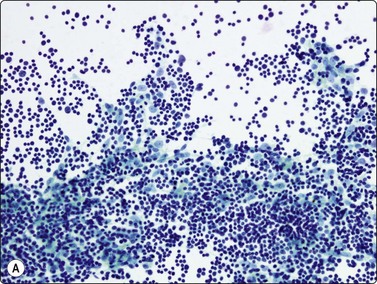

Fig. 9.5 Thymoma, spindle cell

Cohesive tissue fragment; elongated pale, regular nuclei; indistinct cell borders (H&E, HP oil).

image

Fig. 9.6 Thymoma, spindle cell

Tissue section (H&E, HP).

In the benign thymomas, the epithelial cells are usually cohesive (Figs 9.1, 9.5) but may also manifest a reduction in intercellular cohesion (Fig. 9.2). Epithelial cells are not immediately evident in the mixed tumors at low power but are discernible using the higher magnification.18,29,30 The epithelial cells are polygonal, oval, or spindle shaped with uniform to slightly irregular nuclear outlines possibly with cleaved or folded nuclei. Their nuclear chromatin is homogeneous, finely distributed and pale and, occasionally, small nucleoli are seen. Cell borders are indistinct, but nuclei are separated by moderate amounts of pale cytoplasm (Figs 9.2, 9.5). In one personally examined case of thymoma metastatic to lung, Hassall’s corpuscles were evident in the clumps of tumor cells (Fig. 9.4); this is a most unusual manifestation and will not be present in most thymomas. When there is a lymphoid population, the bimodal pattern enables one to make a virtually certain diagnosis.18,29,30 In pure epithelial or spindle cell forms, definitive diagnosis is more difficult, although in Dahlgren’s series29 most thymomas were diagnosed and in Tao’s 37 cases30 all FNAC diagnoses of thymoma were verified histologically. Ali and Erozan34 were able to diagnose all of their 14 cases using a combination of cytology, immunocytochemistry and clinical information, and Shin and Katz showed a high accuracy in a range of mediastinal lesions including 14 thymomas.35 Tao and others describe more variation in the degree of cohesion than we have seen, particularly in pure epithelial/nonspindle cell types.30 Overall, the most challenging and the most common in our experience are the lymphocyte-rich (type B1) thymomas, as the tumor cells may be obscured by the lymphocytes.